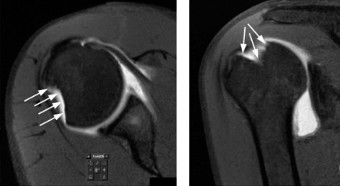

The correct answer is (A). In a young patient, the most likely injury associated with a glenohumeral dislocation is a labral tear (see Fig. 2–31). In an older patient, >40 years old, a rotator cuff tear is more likely. Other possible associated injuries include:

Figure 2–31 MRA demonstrating an anterior labral tear.

A 24-year-old, male athlete sustains an anterior shoulder dislocation. His MRI is shown in Figure 2–32.

Figure 2–32

Discussion

The correct answer is (A). The MRI demonstrates an HAGL lesion. The MR arthrogram shows fluid extending down the medial humerus and is indicative of an HAGL. Most commonly, with an anterior dislocation, the anterior band of the inferior glenohumeral ligament is torn. With a posterior dislocation, the posterior band is torn creating a reverse HAGL. The ligament tends to tear off the humeral side. These are important injuries to identify as arthroscopic labral repair and capsular shift may be unsuccessful without concomitant repair of the HAGL lesion. Many authors advocate an open approach to repair an HAGL lesion.